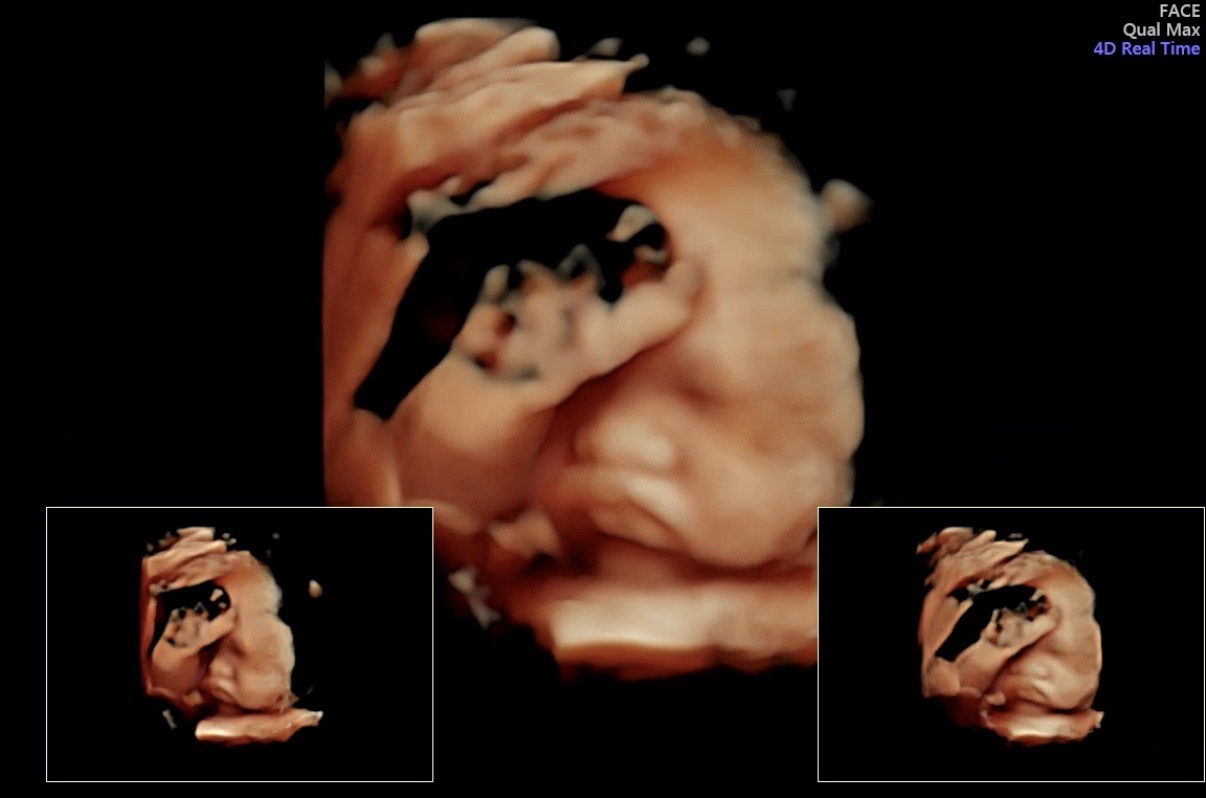

오늘 진료에서는 아기 상태를 먼저 확인하고,